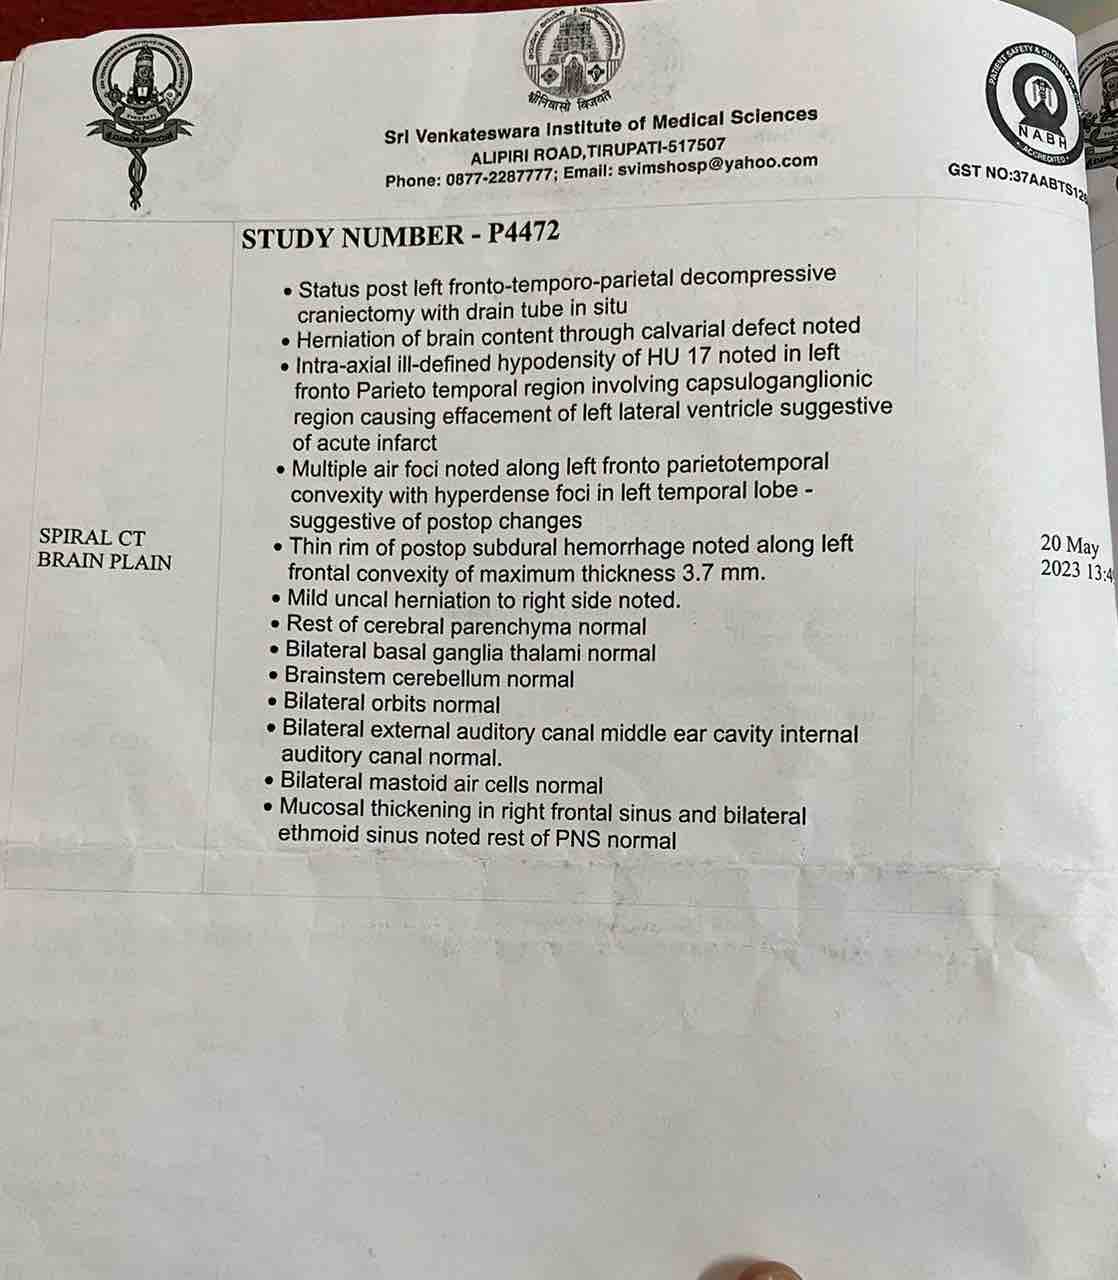

We are reaching out to you today with a heavy heart and a plea for help. Our beloved 66-year-old mother K VIJYA LAKSHMI, has been facing an incredibly challenging journey since 16th May when she had brain stroke & underwent emergency brain and abdomen surgery. Her recovery has been a rollercoaster of ups and downs.

During her hospitalization, she endured multiple complications, including respiratory distress, recurrent severe infections, and even seizure-like activity. Through it all, she has shown immense strength and determination. Still she require three more surgeries to stand on the path of recovery.